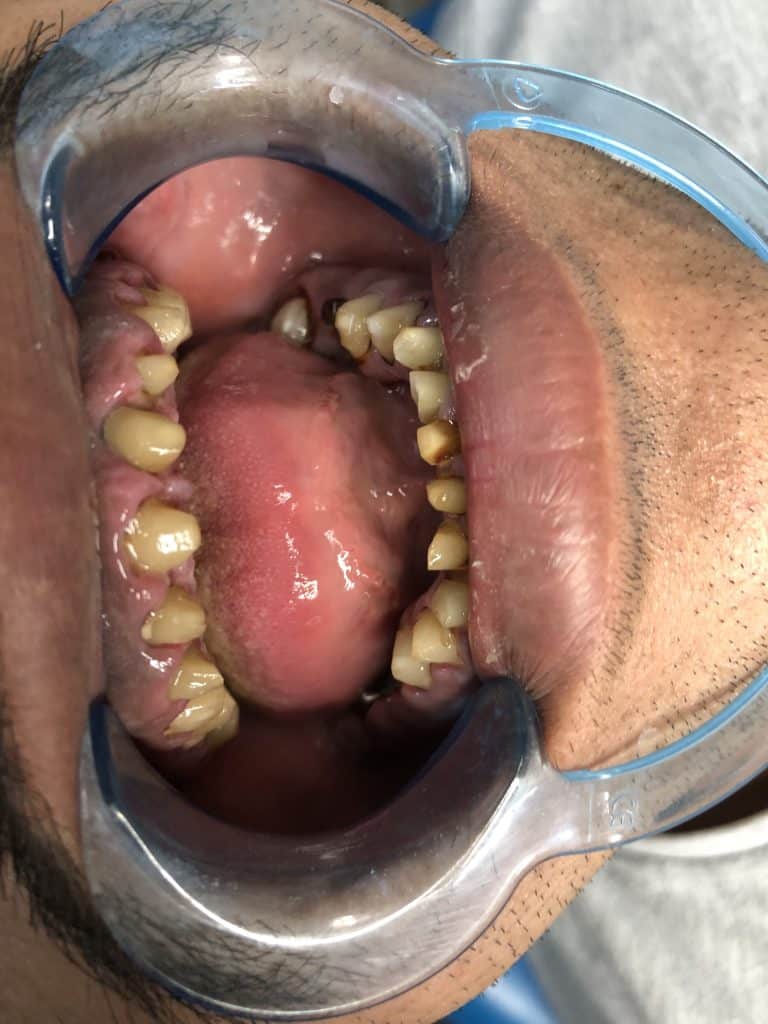

The diagnostic aid : panoramic x-ray , clinical examination .

Gingival diagnosis : there is no inflammation in the ligaments .

2- remove all caries from all teeth , RCT and re RCT for all treated teeth

( 11,12,13,14,15,16,17,21,22,23,24,25,26,27,31,32,33,34,35,41,42,43,44,45)